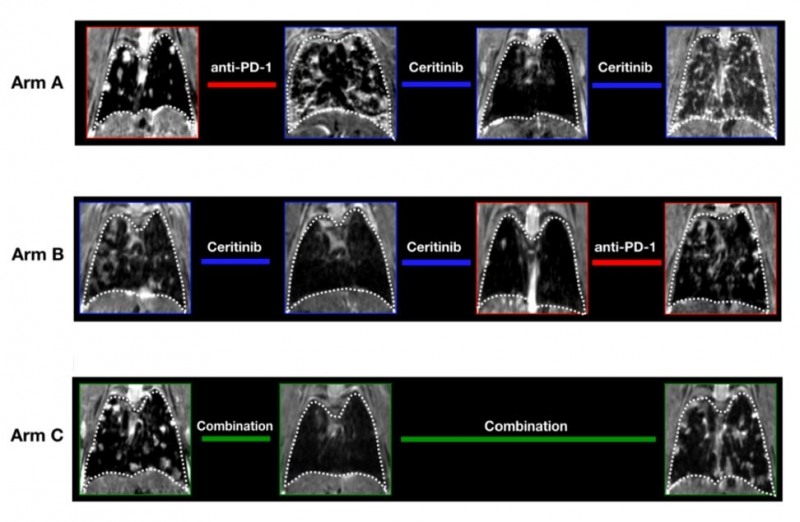

연구팀은 ALK 형질전환 마우스모델을 ALK 억제제와 면역항암제(anti-PD-1)를 단독 투여군과 병용 투여군, 순차적 투여군으로 나눠 약물의 효과와 부작용, 면역 기전을 확인했다.

연구결과 ALK 양성 폐암에서 면역항암제의 경우 종양 억제 효과가 미비한 것으로 확인됐다. ALK 억제제 단독은 효과적이었고, ALK 억제제와 면역항암제 병합요법은 ALK 억제제 단독으로 사용했을 때와 큰 차이가 없었다. 오히려 병합요법에서는 심각한 간독성이 나타났다.